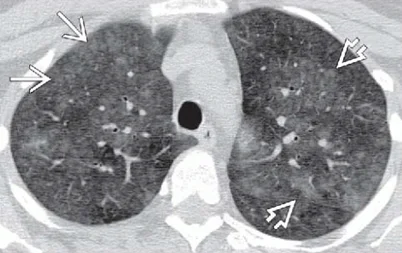

さらにやっかいなことにレントゲンでも,この加湿器肺炎が分かりづらいこともが非常に多いです。そのため病院を受診してもすぐに「加湿器肺炎」が疑われることはほとんどないと思います。色々治療をしてみてもよくならなかったり,症状が長引いたりすることで,もう少し詳しく調べようという発送にいきつきます。そこで初めて登場する検査が,胸部CT検査です。草ヶ谷医院でもなかなか咳が治らない方にたいして,胸部CT検査を追加して実施することがあります。

左が正常の胸部CT写真,右が過敏性肺臓炎のCT写真です。粉雪のような淡い白い影が肺全体に広がっていることがわかります。淡い影のため,レントゲンではあたかも正常のように見えてしまうこともありますが,胸部CTでは見逃すことは

(Case courtesy of Bruno Di Muzio, Radiopaedia.org, rID: 41162)

ありません。この画像を見た場合には,クリニックではできない検査をうけてもらうために総合病院に紹介となります。